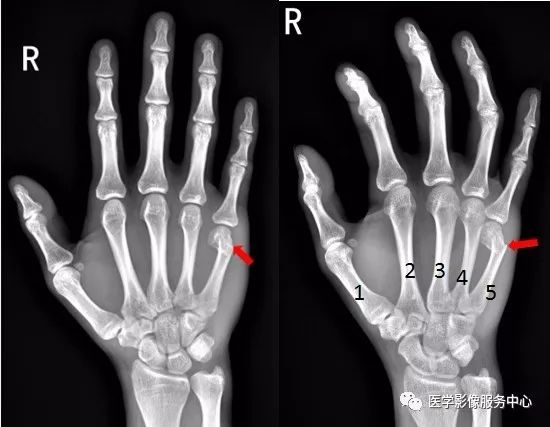

右手第五掌骨远端骨皮质不连续,骨折端移位、成角。右手第五掌骨骨折(1-5. 第1-5掌骨)

右手第四掌骨中段、第五掌骨基底部见横行骨折透亮线,骨折端对位对线尚可。第四、第五掌骨骨折。